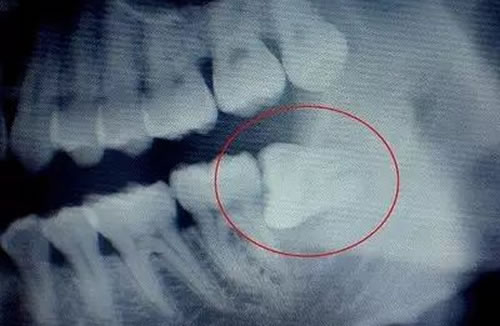

3不正常生长的智齿是什么样?

不正常生长的智齿有:横着的,斜向前的,斜向后的等等奇形怪状都有。

如下图:

横着长的智齿